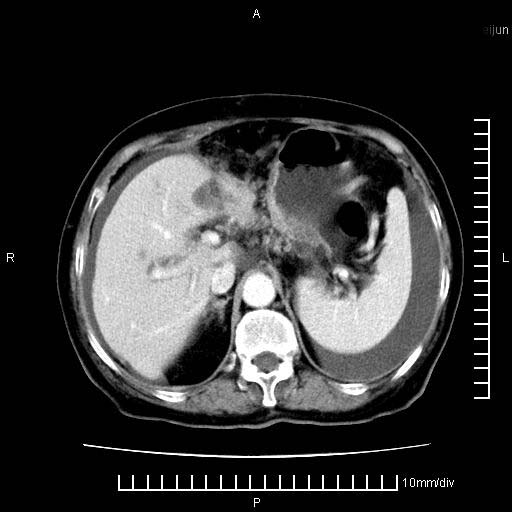

上腹疼痛月余,外院核磁诊断胰腺癌。现临床示右下腹可明显触及包块,可片子上怎么没有看到?

1.胰腺颈体部癌。

胰腺体部癌累及周围器官,腹膜、粘连

1。胰腺ca伴腹膜腔转移

胰腺体部癌累及周围器官,腹膜、粘连,临床摸到的可能是粘的组织

胰腺结构模糊,胰尾部见囊性包块,周围脂肪密度增高,左肾前筋膜增厚,胸水、腹水。不符合胰腺ca伴腹膜腔转移。考虑胰腺炎伴假性囊肿形成、胸腹腔积液。

1)考虑胰腺癌并胰腺假性囊肿形成。2)肝内低密度灶,不排除转移。3)右肾盂积水。4)腹水。5)右侧胸腔积液并右肺下叶部分膨胀不全。